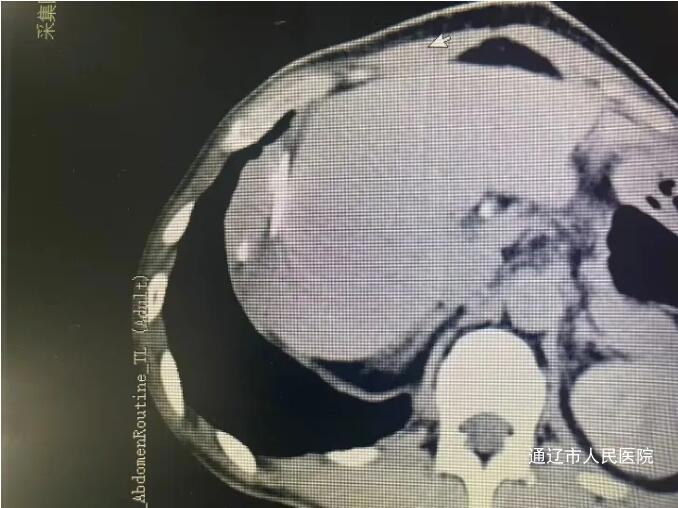

近日,我院肝胆胰外科成功实施了全市首例CT引导下肝肿瘤纳米刀消融术,标志着我院肝胆胰外科在肿瘤微创消融领域迈上新台阶,填补了本地区医疗技术空白。该患者男性,因腹胀于我院就诊,完善相关检查诊断结肠癌伴肠梗阻,肝占位性病变考虑转移瘤,讨论病情后决定一期行腹腔镜下根治性右半结肠切除术,术后复查腹部增强CT、增强肝脏MRI提示肝脏转移瘤有进展趋势,遂行CT引导下肝肿瘤纳米刀消融术。

手术过程中,患者行全身麻醉,在解放军总医院肖越勇教授指导下,我院肝胆胰外科主任医师郭雅明、手术麻醉科副主任医师高飞、CT室医护团队在CT引导下确认病灶位置并进针,确保电极区域完全包裹肿瘤后开始消融。消融过程中电流上升反馈良好,术后即刻增强CT显示消融范围覆盖病灶,周围血管、胆道结构完好无损伤,出现明显气体影,消融效果良好。消融完成后,退出穿刺针,手术顺利结束,术中麻醉效果满意,生命体征平稳,麻醉恢复后无腹痛腹胀,恶心呕吐等不适。术后给予对症支持治疗,患者恢复良好。和传统的消融治疗方式不同,纳米刀消融技术是通过脉冲电场导致细胞不可逆电穿孔,从而实现肿瘤组织杀伤,是一种非热选择性物理消融技术,可在实现消融肿瘤的同时,保留肿瘤周围的重要管道结构(血管、胆管和神经)完整性,并且无热沉效应,消融肿瘤细胞,适用于消融治疗靠近肝门、胆囊、膈肌和结肠等肝脏特殊部位的肿瘤有着独特的优势。纳米刀消融手术为现阶段先进、安全的肿瘤消融技术,它为无法使用传统手术方式的特殊部位癌症患者提供了新的治疗方式,还具有能够选择性消融,时间短、创口小等优点,一定程度上能够改善生活质量,延长生存时间,纳米刀消融对不能手术的肝癌、肺癌特别是胰腺癌具备较大的技术优势。此次全市首例纳米刀消融术的开展,标志我院微创介入技术取得重大突破,也为疑难肿瘤患者提供了更为先进技术的诊疗手段。